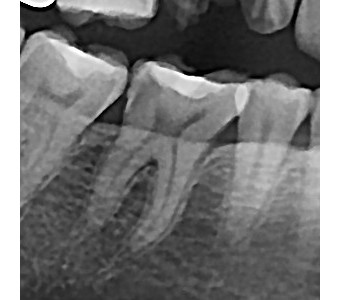

결과로 증명합니다.

국제모아치과의

실제 임상 증례